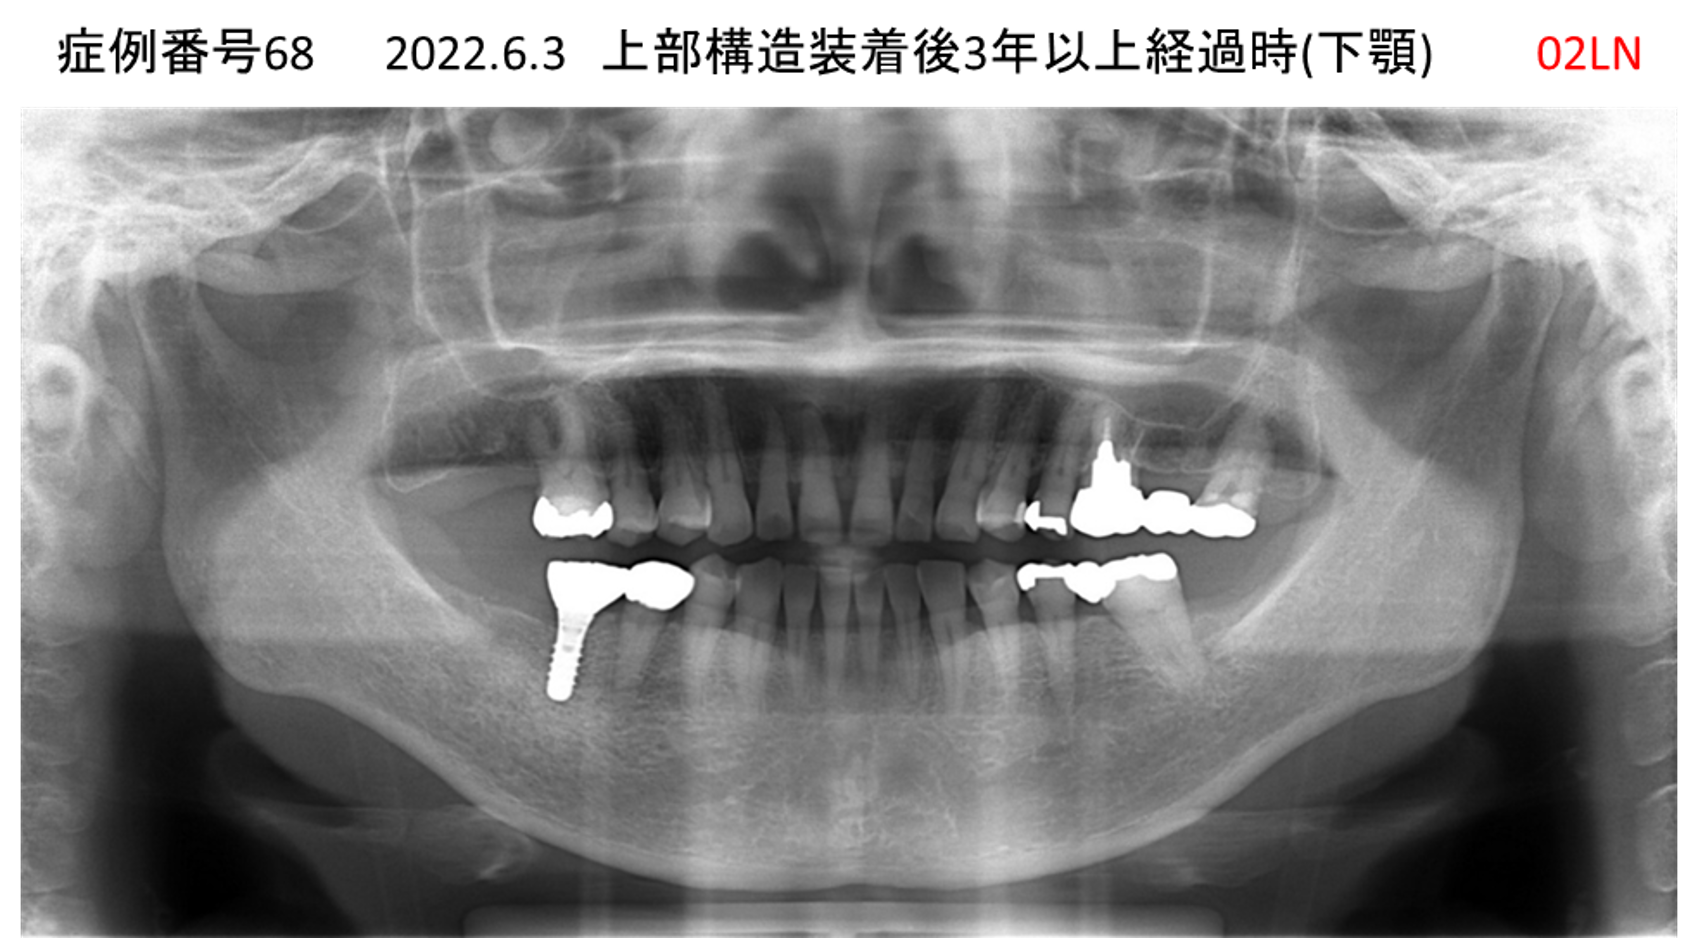

左下の奥歯が痛い患者様のインプラント症例

| 治療名称 |

インプラント |

| 治療費用 |

215万円+税 |

| 治療期間 |

5か月 |

| 患者さんの症状(主訴) |

左下の奥歯が痛い。 |

| 治療内容 |

| 治療結果 |

痛み無く、噛める。 |

| 治療の注意点(リスク/副作用) |

インプラントが壊れたら再治療が必要 |